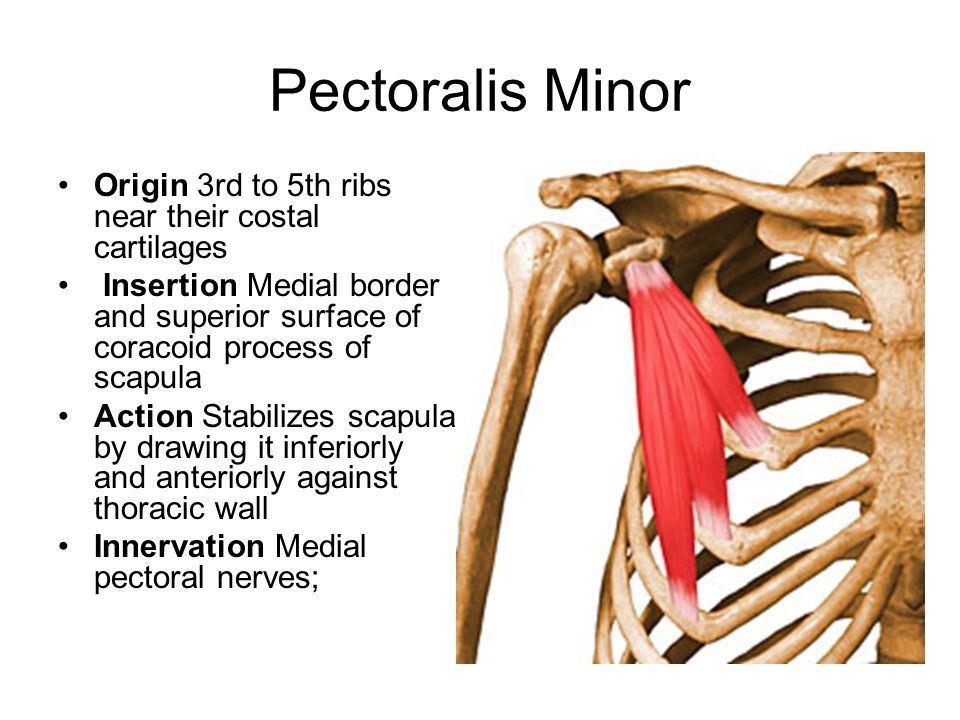

小胸筋

小胸筋